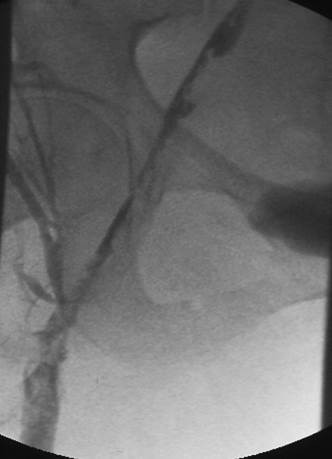

Venograma en posición decúbito prono de la vena femoral izquierda donde se muestra un trombo masivo dentro del lumen de la vena.

Venograma en posición decúbito prono donde se muestra un trombo que obstruye las venas ilíaca y femoral.